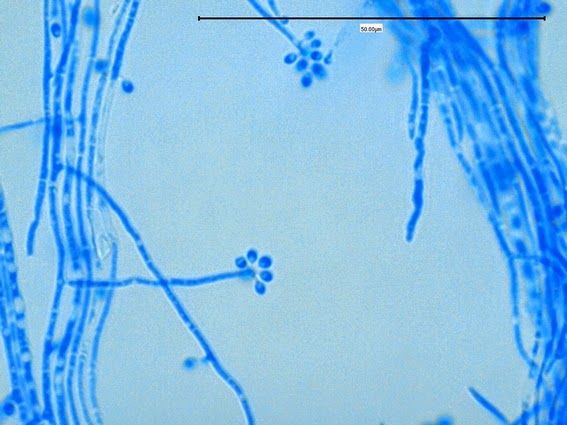

Identify this organism.

Aspergillus fumigatus